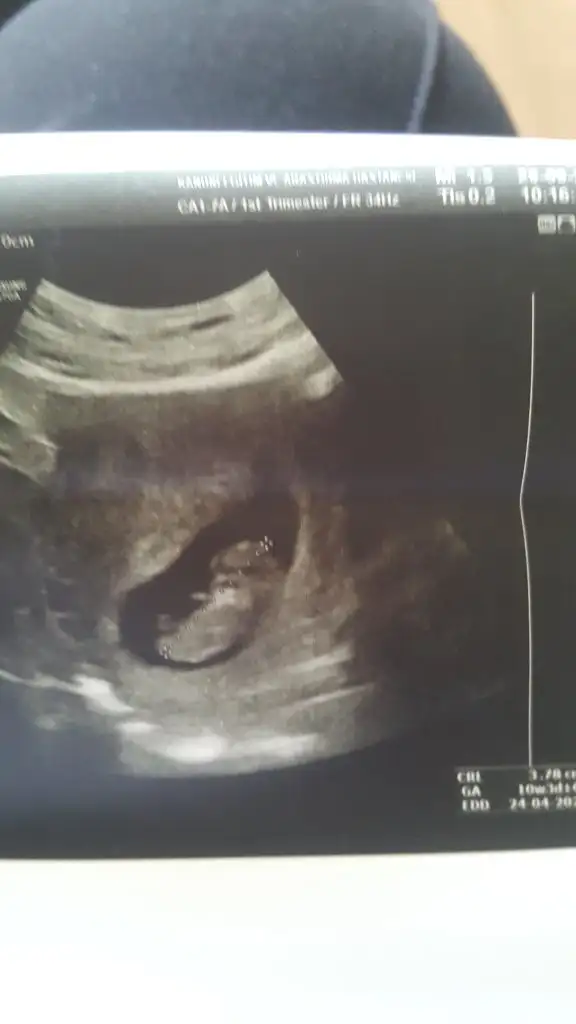

Bana da yorum yapar mısınız vajinal usg 6+6

• 03B2C2FF-740C-448A-BAF2-933D726BF0E7.webp

03B2C2FF-740C-448A-BAF2-933D726BF0E7.webp

31,7 KB · Görüntüleme: 101